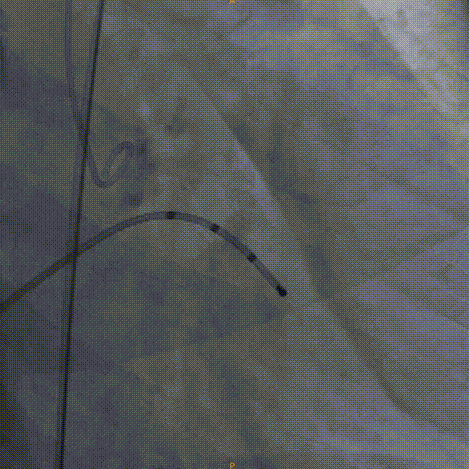

主动脉根部造影:左右冠灌注情况良好,瓣叶活动度一般,无明显反流。

20mm球囊预扩:冠脉灌注情况良好,瓣上结构改变,微量反流。

Venus26号瓣膜定位:结合瓣上结构考虑,采用0位释放。

Venus26号瓣膜释放:前三分之一慢放精准定位,中三分之一快放使瓣膜快速进入工作状态。